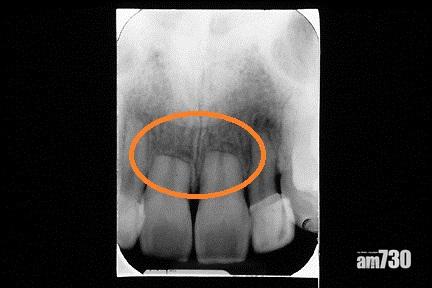

矯齒治療前

矯齒治療後門牙有牙腳收縮現象(此為嚴重收縮病例)。